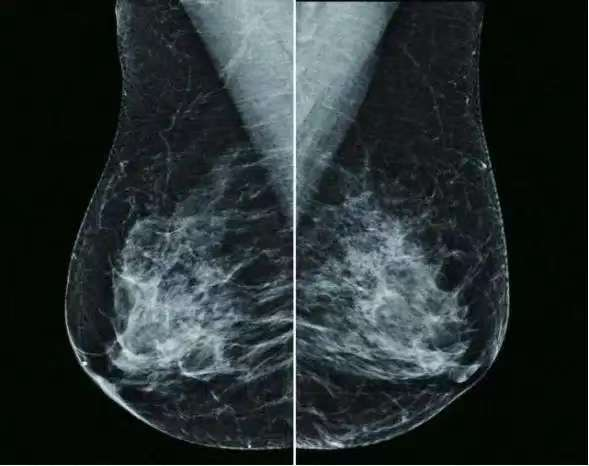

一、什么是乳腺X线摄影?

乳腺X线摄影是一种利用低剂量X射线对乳腺组织进行成像的医学影像学检查方法。它利用特殊的X光机拍摄出乳房的影像,医生通过这些影像观察乳腺结构是否正常,是否存在肿块或其他病变。

二、乳腺钼靶摄影有哪些特点?

1. 早期发现:乳腺X线摄影能够检测出体格检查触摸不到的乳腺肿块,特别是对于大乳房和脂肪型乳房。它还能观察到小于0.1毫米的微小钙化点,对乳腺癌的诊断敏感性和特异性都很高。

2. 无创性检查:乳腺X线摄影相对无创,简便易行,且分辨率高,重复性好,留取的图像可供前后对比。